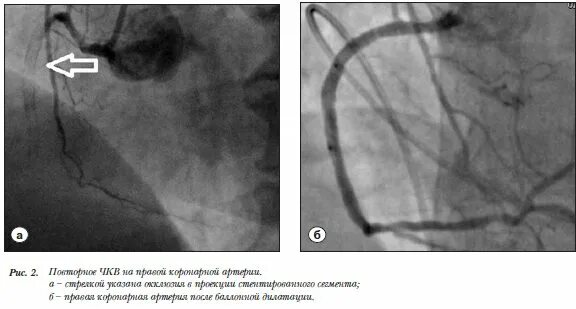

Чрескожное вмешательство на коронарных артериях. тромбоз подвздошной артерии узи. пульсирующая гематома бедренной артерии на узи. пульсирующая гематома бедренной артерии после стентирования.